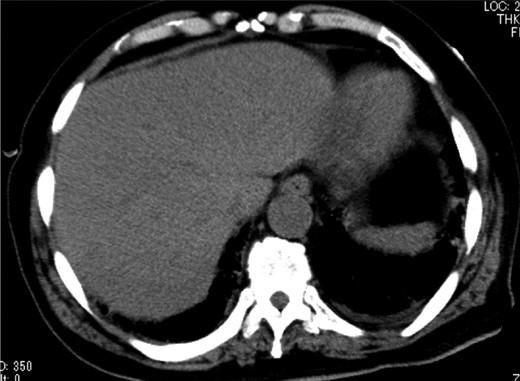

A 79-year-old man with acute abdominal pain had gone to a nearby hospital. As HPVG was detected by abdominal computed tomography (CT), he was transferred to our hospital for further examination and treatment. He had no remarkable past medical history. When he arrived at our hospital, his vital signs were relatively stable (body temperature: 37.2°C; blood pressure: 112/74 mmHg; pulse rate: 68 beats/min). However, physical examination revealed abdominal distention, rebound tenderness and abdominal guarding as signs of peritoneal irritation. The laboratory findings indicated acute inflammation (white blood cell count of 18 400/μL and Creactive protein concentration of 17.7 mg/dL), dehydration and metabolic acidosis (a level of base excess of −7.0 mmol/L). Creatine kinase was remarkably elevated (28 327 IU/L) (Table 1). Plain abdominal radiographs showed distention of the small intestine and suggested subileus (Fig. 1). Contrast-enhanced abdominal CT revealed HPVG (Fig. 2a), a contrast defect in a region of the small intestine, and a small amount of ascites around the intestine. There was no thrombus in any artery; however, the wall of the appendix was moderately thickened when we reevaluated the images retrospectively (Fig. 2b). We performed an urgent laparotomy with the diagnosis of generalized peritonitis caused by intestinal necrosis. A small amount of turbid ascites and a dilated small intestine were observed in the peritoneal cavity. Although the entirety of the small intestine and colon were explored, no intestinal ischemia was detected. Then, we found discoloration of the appendix with wall thickening. We thus made a clinical diagnosis of peritonitis caused by gangrenous appendicitis. Although the appendix wall was fragile, no macroscopic perforation of it was observed. We performed appendectomy and abdominal drainage. Based on the pathological findings, the patient was diagnosed with gangrenous appendicitis, with no evidence of malignancy (Fig. 3). Escherichia coli was positive in the ascitic culture. After the surgery, intravenous antibiotic treatment (meropenem) was administered. The patient subsequently went into septic shock with disseminated intravascular coagulation (DIC). He was therefore admitted to the intensive care unit (ICU), where he received blood purification therapy. The CT images on Day 7 after the surgery showed that HPVG had disappeared (Fig. 4). He left the ICU 7 days after the surgery and was discharged from the hospital another 10 days later.

Abdominal CT on Day 7 after the surgery showed that HPVG had disappeared.